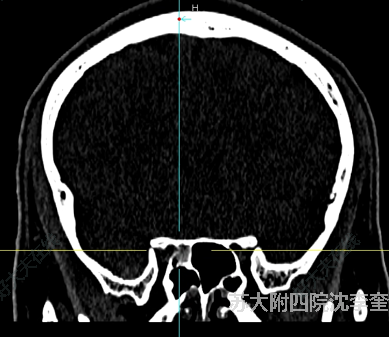

治療前患者影像特征比較明確,傷后迅速出現(xiàn)視野缺損,考慮患者局部骨質(zhì)肥厚,骨折呈擊出性骨折,考慮力量較大,同時可見氣房內(nèi)出血,后續(xù)水腫加重可能比較大需要手術(shù)減壓。治療后治療后即刻患者視神經(jīng)管擊出性骨折,伴有onodi氣房積血,結(jié)合其自身影像學(xué)特點,先打開onodi氣房,再開放同側(cè)蝶竇,最后開放對側(cè)蝶竇后徹底磨除眶尖、視神經(jīng)管內(nèi)上壁及內(nèi)下壁,顱口后徹底減壓。術(shù)后患者上側(cè)視野較術(shù)前清晰,視力進一步改善。